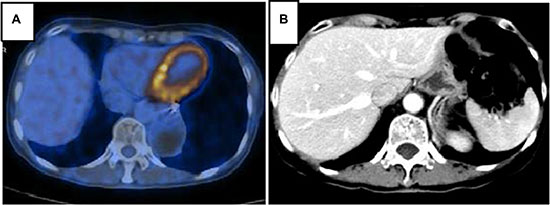

Nevertheless, two months later, the patient was referred to our medical consulting room. The level of CEA increased once again following decreasing after the gastric surgery. We performed a FDG-PET/CT due to her CEA 146 ng/ml and baseline nuclear medicine scan. The FDG-PET/CT performed on April, 2013 showed multiple malignant lesions in her liver and suggested liver metastases (Figure 5). She refused liver biopsy. Considering her medical history and imaging findings, the liver lesions were diagnosed as metastases from primary lung carcinoma. She started on oral erlotinib (150 mg, on an empty stomach) for her advanced-stage EGFR exon 19 mutation-positive lung adenocarcinoma from April, 2013. CEA in following up gradually declined to normal until September, 2013. Unexpectedly, tumour assessment by FDG-PET/ CT on 17th February, 2014 using RECIST showed a complete response (CR) (Figure 6A). During the period of erlotinib treatment, chest and abdominal CT was performed every two months and showed radiology CR (Figure 6B). Assessments of toxic effects using NCI-CTCAE showed grade 2 neutropenia and grade 2 fatigue. The patient has taken oral erlotinib for 40 months and is still going on oral erlotinib treatment. She was controlled conservatively and survived for a good quality of life.

Figure 5: PET/CT scan showing multiple malignant lesions in the liver and suggesting liver metastases.

Figure 6: PET/CT (A) and CT with contrast (B) in follow-up care showing liver lesions disappeared after erlotinib therapy and achieved CR.